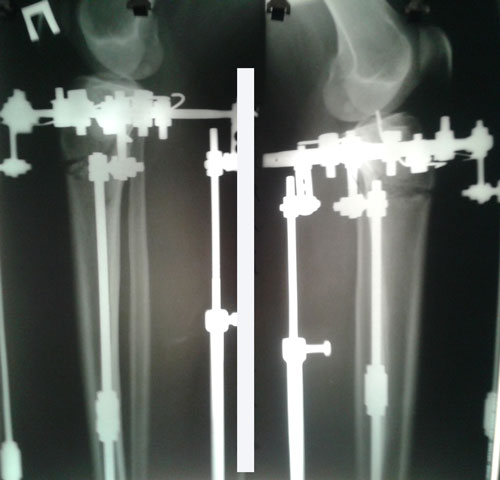

всем привет!выше фото моих ног во время круток))

левую ногу будут крутить дальше,а правая будет отдыхать,я сегодня не сдержалась и измерила свой рост, до операций было 162 см,сейчас 163.5см,классно на 1.5см стала выше))))